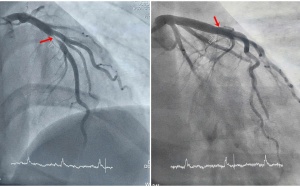

Xơ vữa động mạch là một trong những bệnh lý tim mạch phổ biến và nguy hiểm hàng đầu hiện nay. Điều đáng lo ngại là bệnh thường tiến triển âm thầm, không gây triệu chứng rõ ràng...